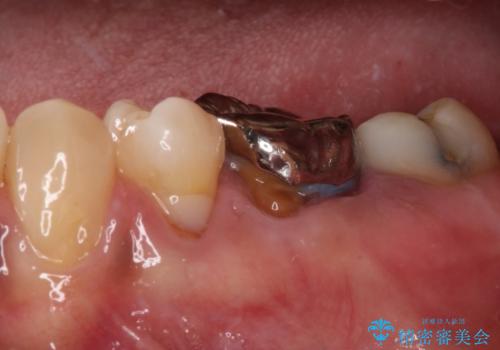

- 矯正治療後に、下顎奥歯の銀歯をすべてゴールドにすることを希望された患者様です。

セラミッククラウンやセラミックインレーによる補綴治療も提案しましたが、お友達にゴールドを自慢したいとのことで、ゴールドクラウンとゴールドインレーにて処置することとしました。